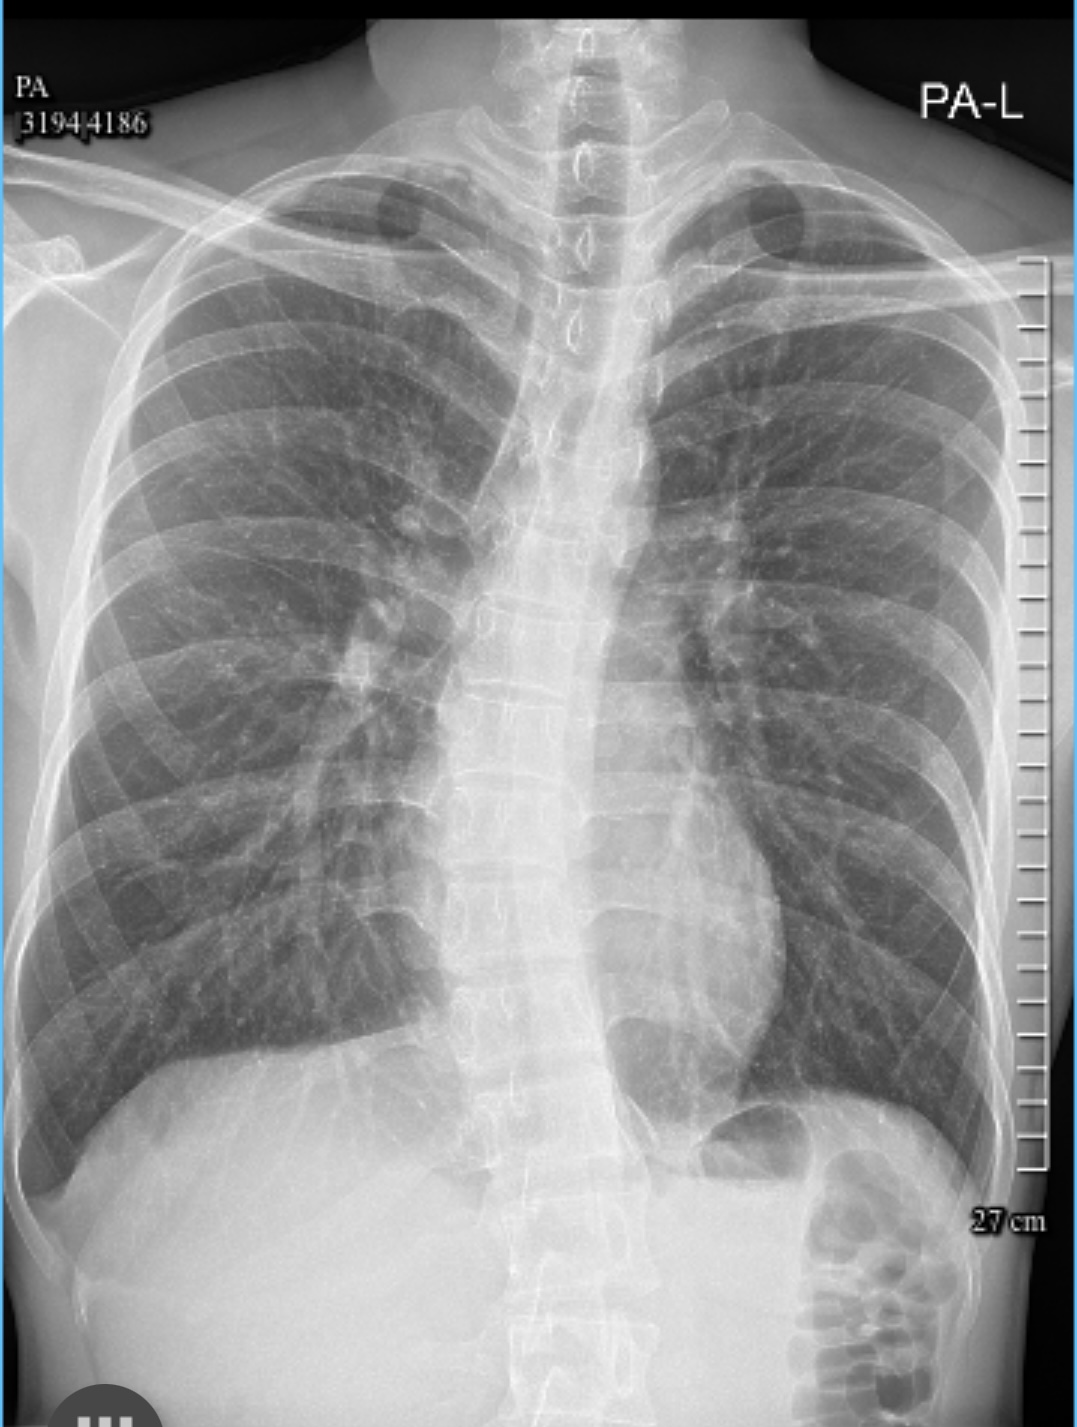

สวัสดีทุกคนครับ 🙏🏻เมื่อวานนี้ ผมเพิ่งไปตรวจที่ รพ.รัฐ(มหาราชนครเชียงใหม่) เนื่องจากมีอาการปวดร้าวลงขา เเละชาบริเวณก้น+รอบๆรูทวาร เพราะช่วง2-3เดือนที่ผ่านมา ไปฝึกงานเเล้วได้ยืนเกือบตลอดทั้งวัน วันละประมาณ7-8ชม เเล้วก็มีอาการปวดหลังเรื้อรังมานานเเล้วครับ นั่งนานๆประมาณ2ชม ก็จะเริ่มปวดหลังล่างมากๆ  เดิมมีประวัติกระดูกสันหลังคดมาหลายปีเเล้ว(เเต่ไม่เคยรักษา) หมอทำ Whole spine x-ray เเละวัดองศาความคด บริเวณทรวงอกคด 33 องศา เอว 27 องศา ออกใบรับรองเเพทย์มาให้ พร้อมกับ CD-X-ray หมอให้ยามากินเเละสั่งจองคิวทำ MRI น่าจะได้คิว2-3เดือน ในใบสั่ง MRI ระบุว่าเป็น หมอนรองกระดูกสันหลังทับเส้นประสาท(HNP Lumbar) เเต่ว่าในใบรับรองเเพทย์ระบุเเค่ตามรูปนี้ (เพราะยังไม่มีผล MRI มายืนยัน) สรุปเอกสารที่ผมมีตอนนี่คือ